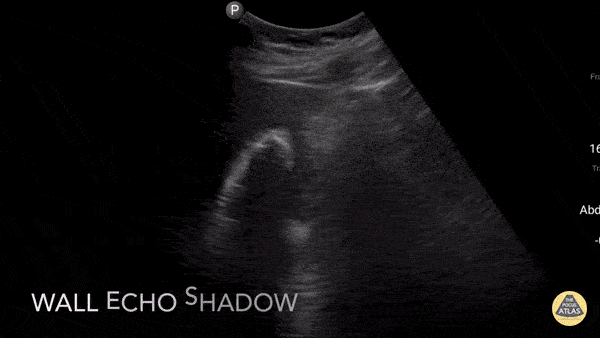

Biliary - Wall Echo Shadow

Pt with epigastric pain, elevated LFTs and lipase. U/S shows the whole gallbladder shadowed by a large calcified stone or "wall echo shadow-WES." The novice may not be able to find the GB and can mistake WES for bowel (but bowel does not shadow like this). Dr. Gordon Johnson